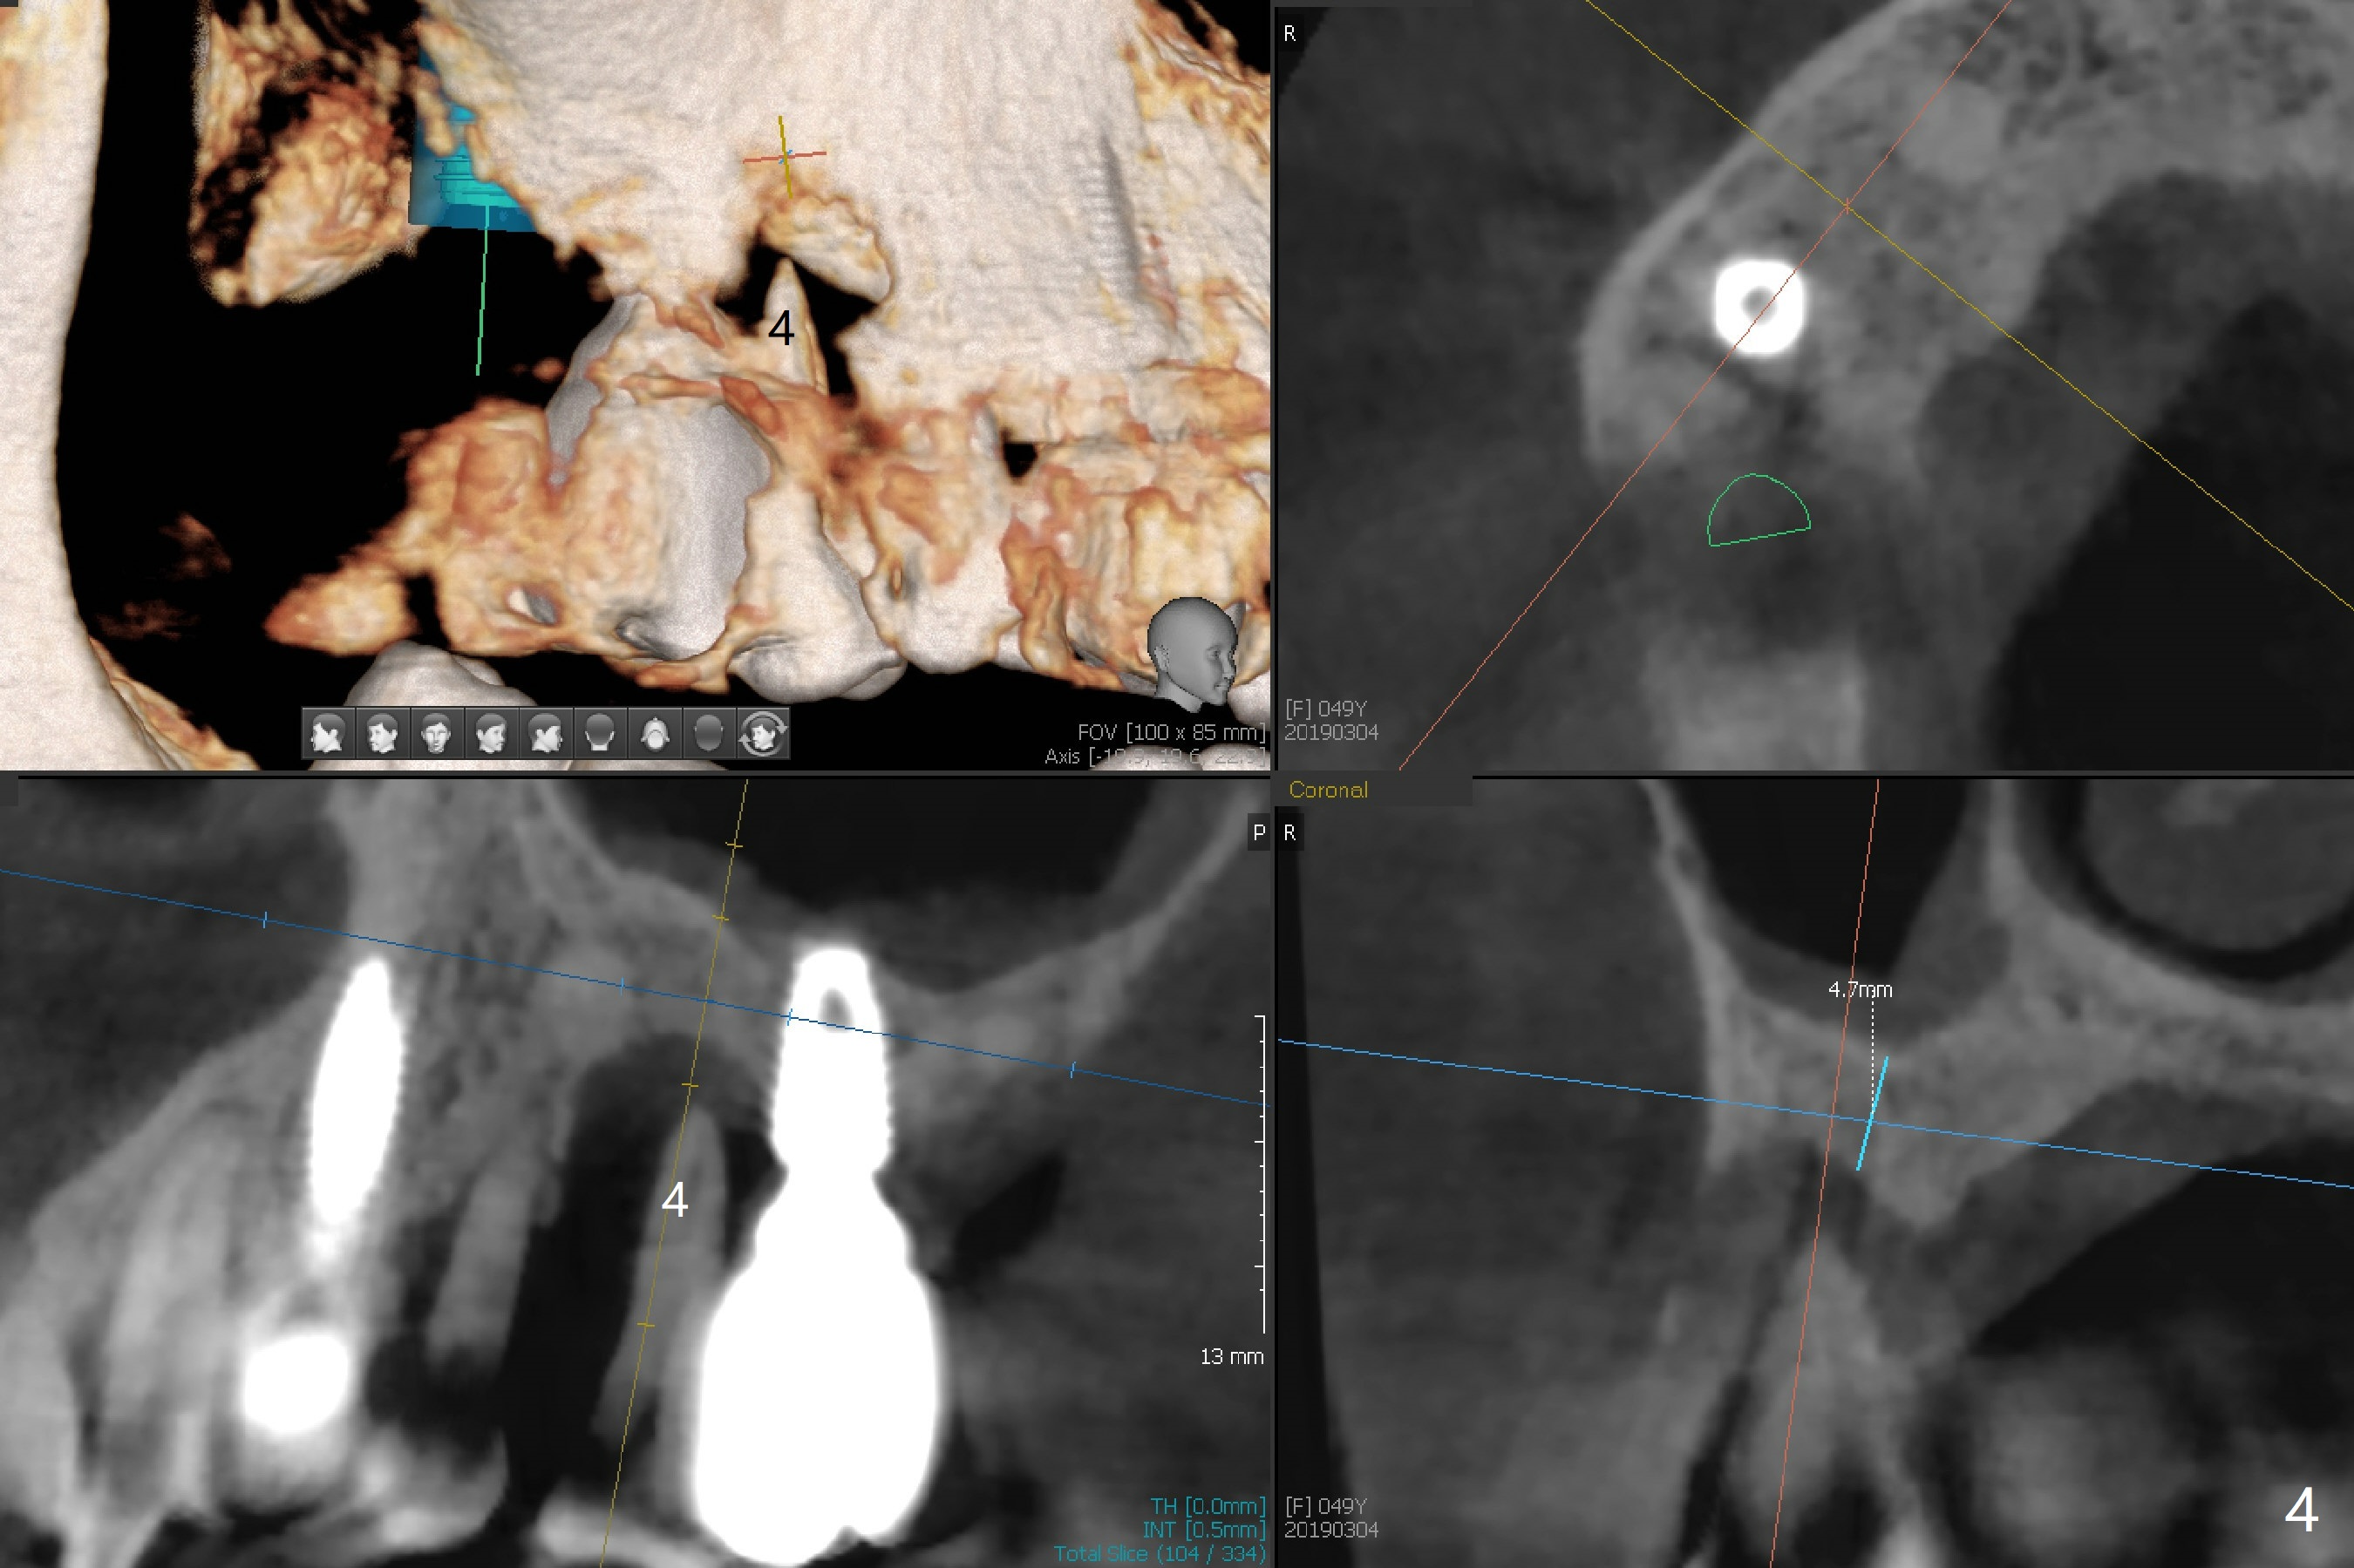

Implant